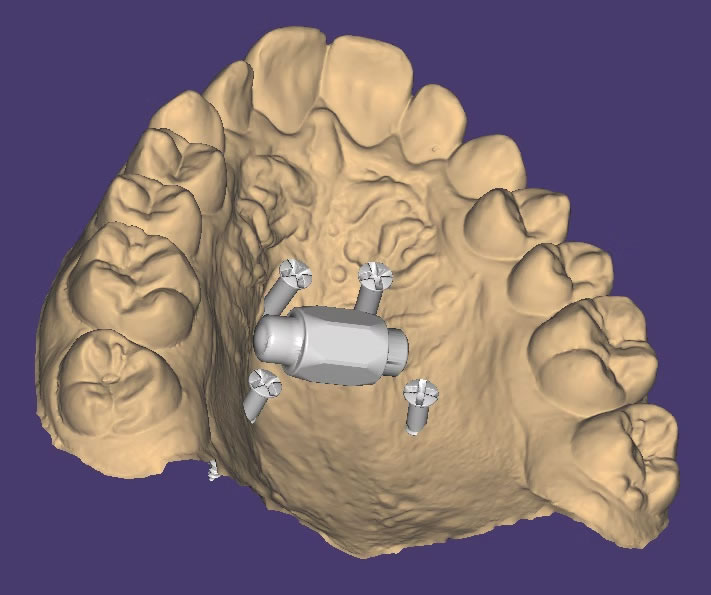

DISYUNTOR MARPE SINTERIZADO

DISYUNTORES SINTERIZADOS

ANCLAJE ANTERIOR